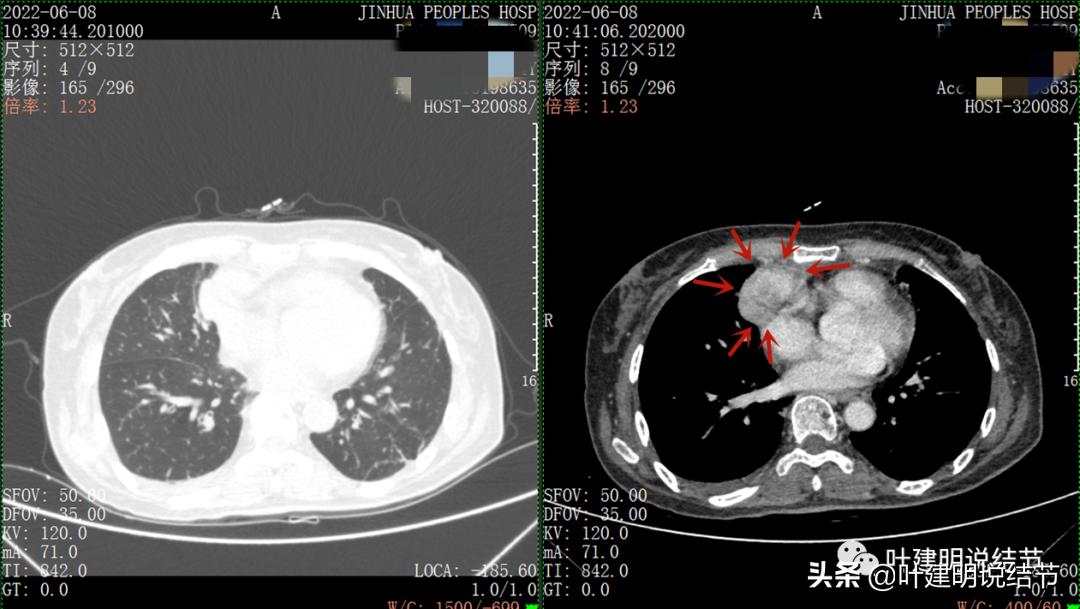

以下图片左侧是肺窗,右侧是纵隔窗。红色箭头示病灶,桔色箭头示无名静脉,黄色箭头示支气管,砖色箭头示上腔静脉,蓝色箭头示主动脉,紫色箭头示肺动脉。

病灶占据前纵隔从上到下全程,多中心,密度不均,对心脏与大血管有压迫,没有明显侵犯

病灶表面不平,中间有坏死

特别显示与无名静脉的关系

上图示最大横断位达5厘米